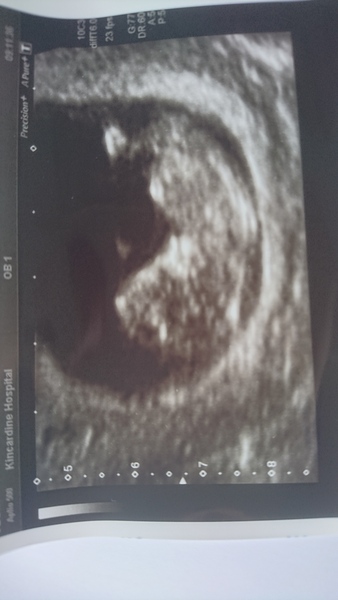

10 +4 at the scan so rough date of 7th Feb got another scan in 2 weeks

Lovely scan @twiglet Smile

Thanks I didn't realise it was the wrong way until it came up on here!

I'm just glad everything is OK and I get a bonus scan in 2 weeks time Smile

Congrats @twiglet. Lovely photo.

Lovely scan photo @twiglet